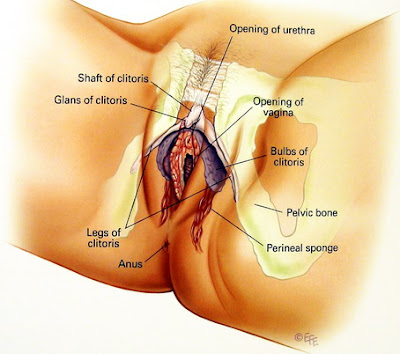

这张图可以更清楚看出阴蒂脚的位置 (白色八字型部分)

紫色部分为阴蒂球

下方红色条状物 Perineal Sponge 为会阴海棉体

想要制造高潮 可以尝试轮番刺激这些部位

阴蒂脚连着阴蒂体向下延伸,并分裂成两个圆柱状物向两旁伸出

将阴蒂体固定在耻骨位置上,长度约有 5~9公分,在兴奋时它也会充血勃起。

阴蒂球:一样是由海棉体所组成

围绕于尿道上方然后分裂成两个小球分列于阴道两侧